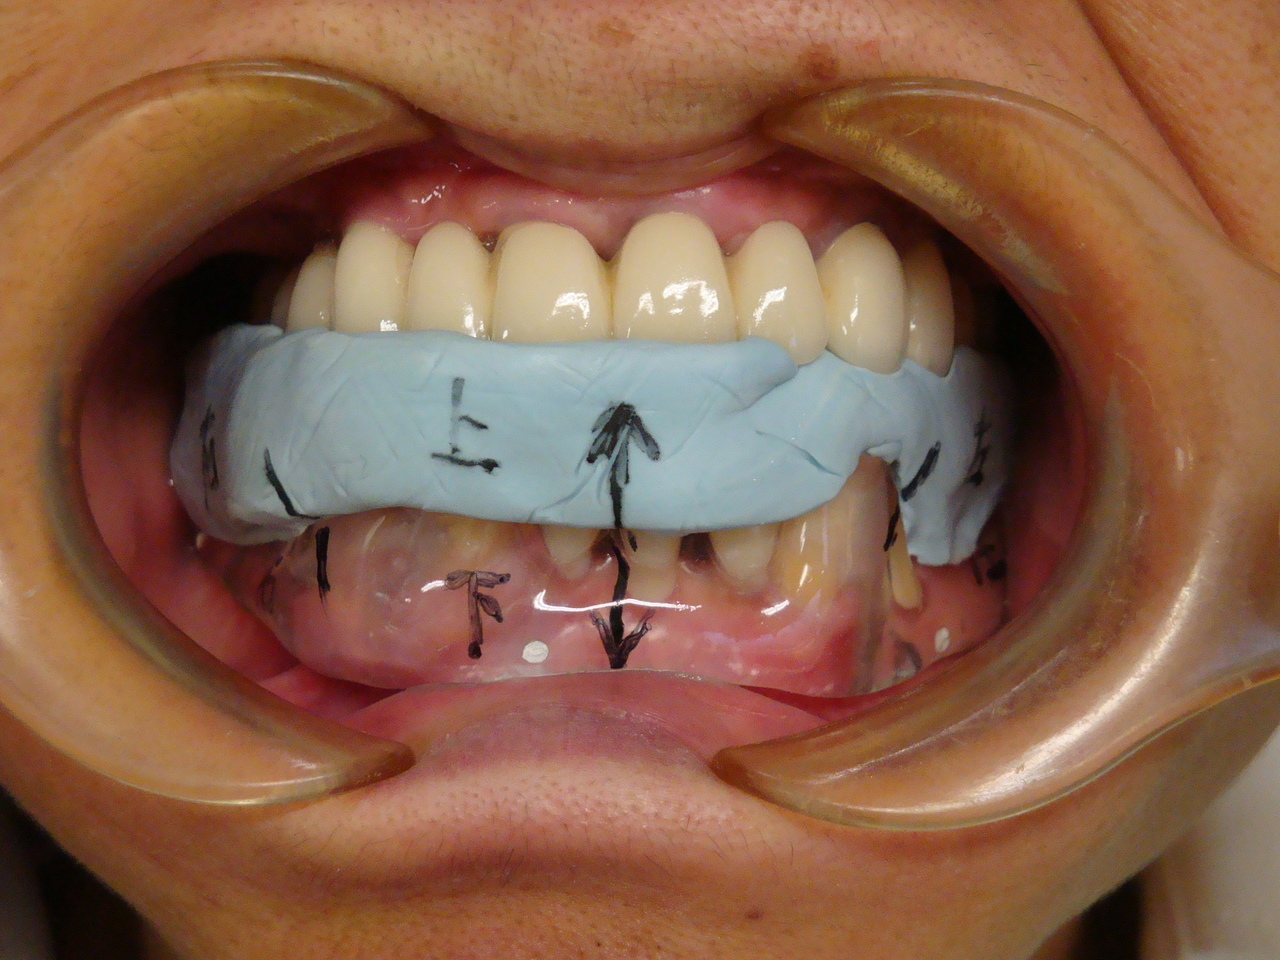

埋入ガイド

CT画像上にて決定した埋入位置で製作された埋入ガイド。正確でスムーズな手術を行えます。

仮歯

埋入位置に合わせた仮歯を製作します。

仮歯装着①

インプラント埋入後、その日に用意していた仮歯を装着します。

仮歯装着②

仮歯をネジ止めして固定します。

これはまだネジ穴を塞いでいない状態です。